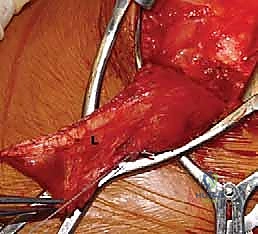

FIG 1 • A. Cadaveric dissection showing the interval between the teres major (TMa) and latissimus dorsi (L) tendons, with the radial nerve (R) deep to the latissimus and the axillary nerve (Ax) superior.

FIG 1 • C. Cadaveric dissection of the superficial muscular anatomy of the posterior shoulder, showing the axillary nerve (Ax) exiting the quadrilateral space.